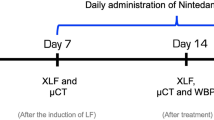

The studies performed in WMS groups A and B differed in experimental design and protocol. The study of group A WMS focused on feasibility of validating pulmonary CT biomarkers with histopathology. In performing these initial experiments, study weaknesses were identified and addressed by developing improved methodology. The improved protocol was then used for a second round of experiments, performed in group B WMS. Methodology differences between the groups are highlighted throughout the following section and include improved dose distribution placement, improved spatial localization of regions of interest (ROI), and expansion of both the number of ROIs and histopathology performed in each ROI.

CT Imaging

All ten WMS received CT imaging both pre- and three months post-RT. During CT imaging, WMS were sedated to significantly reduce motion artifacts and mechanically ventilated to control subjects’ breathing patterns. At each time point, subjects received three types of scans: maximum inspiration breath-hold (MIBH), four-dimensional CT (4DCT), and dynamic contrast-enhanced perfusion scans. The pre-RT MIBH scan was used for treatment planning and tracking distances to pathology points of interest. Pre- and post-RT 4DCTs and contrast scans were used to derive ventilation and perfusion information, respectively. During 4DCT acquisition, subjects were mechanically ventilated to a consistent tidal volume of 1 liter (L) and respiratory rate of 15 breaths per minute (BPM), matching the average tidal volume and respiratory rate of human subjects, and dynamic contrast CTs were acquired with the subject in a max inspiratory breath hold. Breath-hold maneuvers were achieved by setting the mechanical ventilator to maintain constant pressure. 4DCT acquisition and reconstruction methodology are detailed in Wallat et al.17. The dynamic contrast scan procedure is described in Wuschner et al.19.

Radiation treatment delivery

All ten subjects underwent a five-fraction stereotactic body RT (SBRT) course of 12 Gy per fraction, totaling 60 Gy. Treatment planning and dose calculation were performed on the pre-RT MIBH CT. Treatment fractions were delivered following a standard clinical SBRT schedule, with one day between each fraction during weekdays and two days over the weekend. Subjects were mechanically ventilated to eight BPM during treatments with inverted breathing to hold inhale longer than exhale. While each group received the same total dose and fractionation scheme, the two groups of pigs were treated at different anatomical locations with different treatment machines. Treatment differences between the groups described by Wuschner et al.44 are summarized as follows.

Post-mortem histopathological analysis was performed on a section of lung taken from each of the analysis points described in Table 1. Following euthanasia, the lungs were removed from the subject and immediately re-inflated and filled using a formalin solution. A catheter was placed down the main bronchi and a syringe was used to push formalin through to fully expand all lobes to their in-vivo max-inspiration inflation level as much as possible. Once the desired inflation was achieved, the main bronchi were tied to prevent leakage and the lungs were placed in a bath of formalin such that they could float and avoid deformation prior to trimming. For group A subjects, necropsy was performed within a month following the 3-month post-RT CT imaging. Lungs were preserved for roughly one year before histopathology could be performed. Group B subjects experienced an expedited timeline; necropsy was performed within a few days of 3-month post-RT imaging and lungs were preserved for approximately six months prior to histopathology analysis.